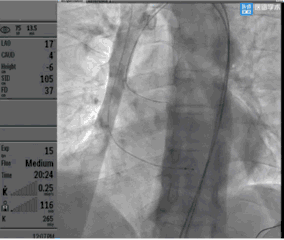

Taurus输送器顺利过弓

瓣膜释放过程稳、准、快,释放后定位可,形态佳,工作正常,平均压差6mmHg

这是一例有示范意义的AS患者瓣膜植入术,患者主动脉瓣根部钙化明显,呈中心聚集形态,主动脉弓部及外周血管钙化轻微,使得术者能专注于根部病变的处理。钙化的集中,为入路建立和器械过弓带来便利的同时,也对最终瓣膜的工作形态带来了很大的不确定性。所以球囊预扩在本病例中,有着很高的数据价值。一般而言,瓣上钙化很严重的情况下,存在downsize两个型号的可能。患者瓣环平均径24.6mm,术前评估downsize一个型号,推荐预装AV26瓣膜。术中经TaurusAtlas 20mm球囊预扩,钙化推移明显,适于植入AV26号瓣膜,验证了术前评估的正确性。